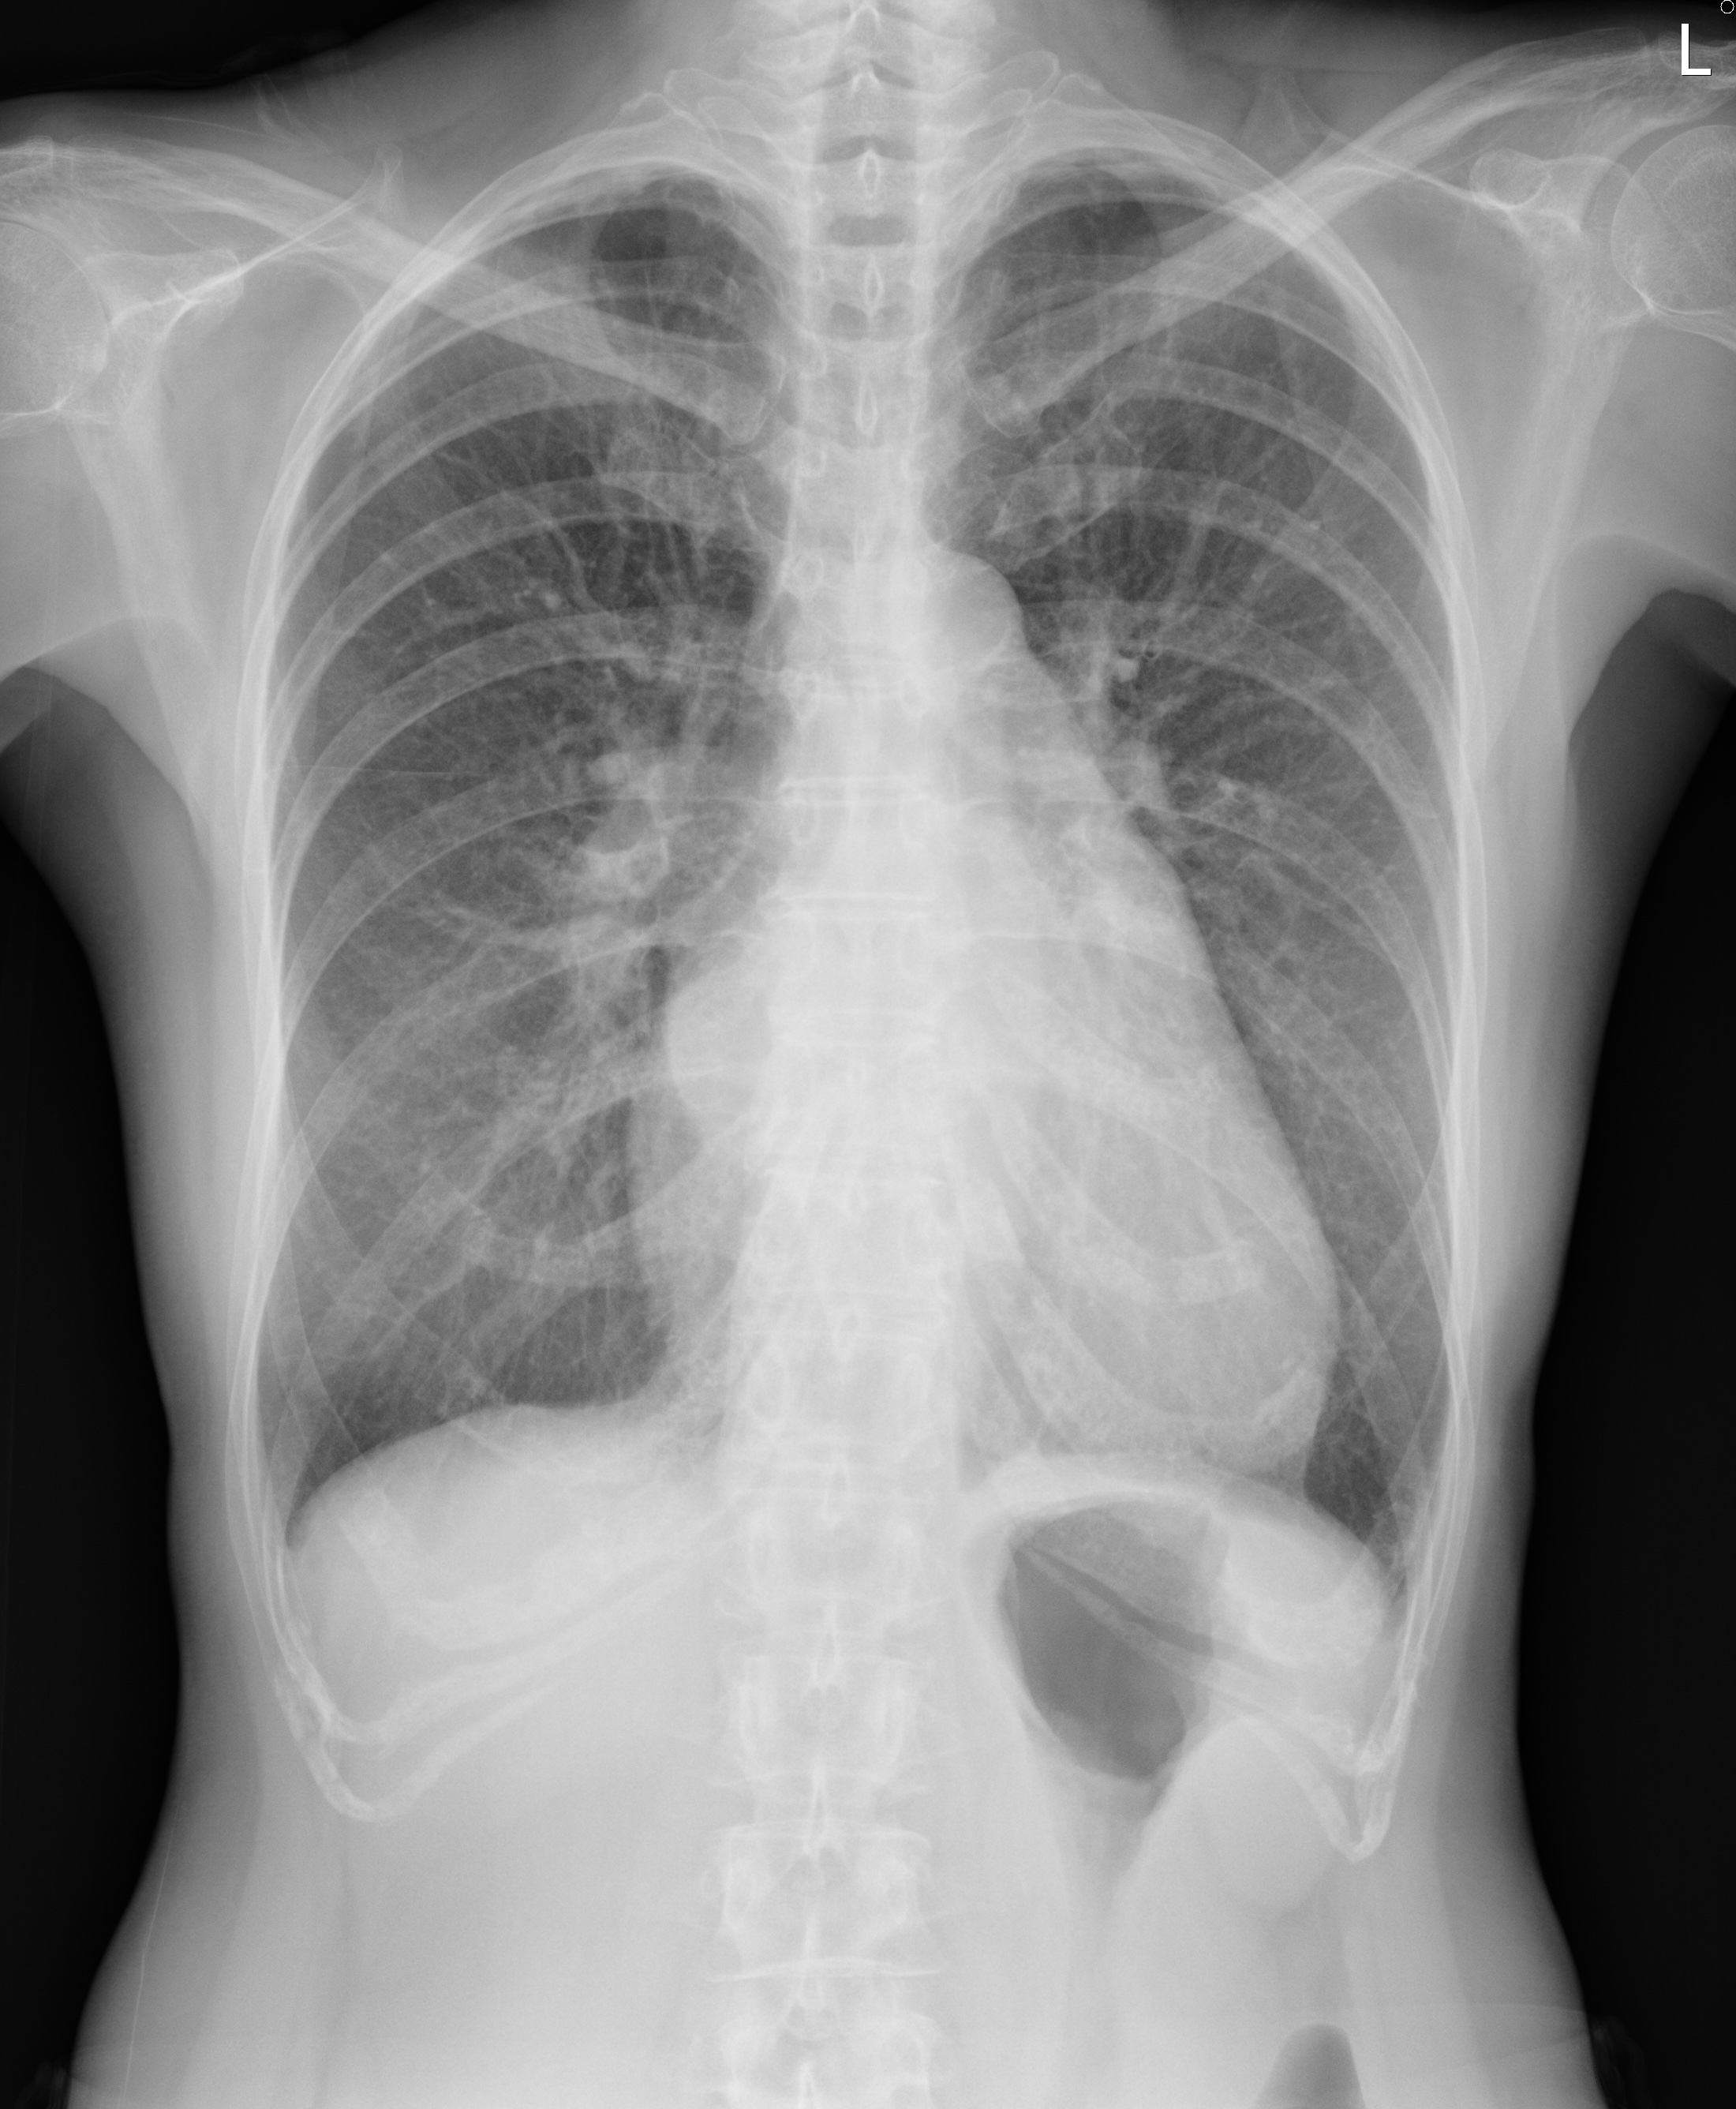

The ECG showed sinus rhythm, first degree AV block, and bi-atrial enlargement. The chest radiograph showed left atrial enlargement with double contour sign. Trans-thoracic echocardiography showed dilated left atrium, adequate global LV systolic function, moderate pulmonary hypertension (estimated PASP 64 mmHg). Commissural fusion and diastolic doming of mitral valve leaflets were present. The mitral valve area was measured 1.03 cm^2, compatible with severe rheumatic mitral stenosis.